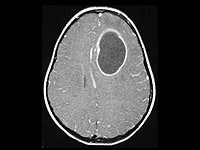

El sistema inmunológico y la terapia genética erradican un tumor cerebral

Un equipo de investigadores ha conseguido erradicar un tipo de cáncer cerebral muy agresivo, el glioblastoma multiforme, en ratones de laboratorio gracias a la combinación de la acción del sistema inmunológico con una terapia genética y química.